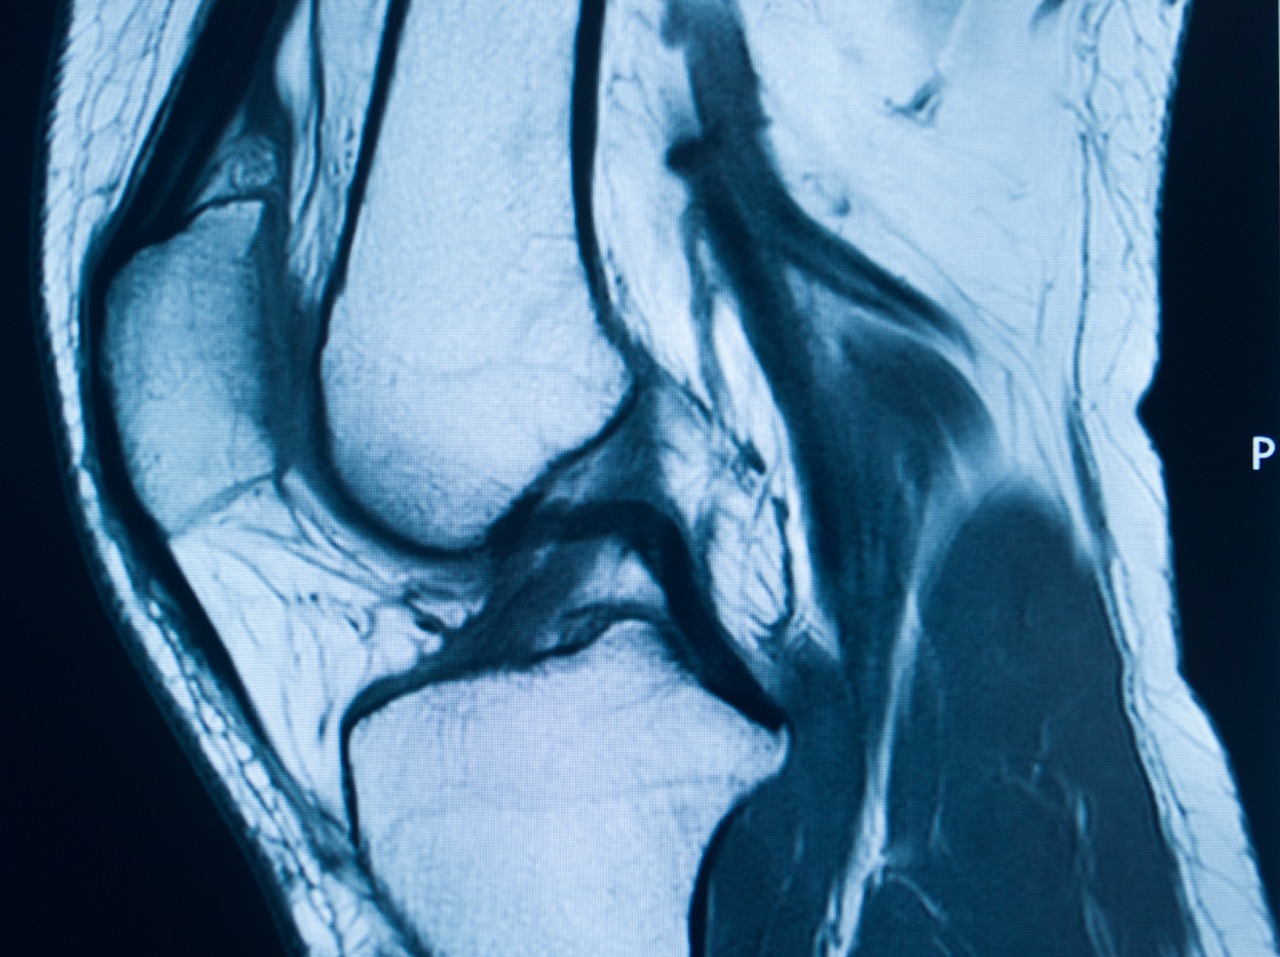

ACL Tear MRI Scan: Know When You Need One

When to Get a Knee MRI for ACL Injury A sudden pop during sports, followed by sharp knee pain, signals